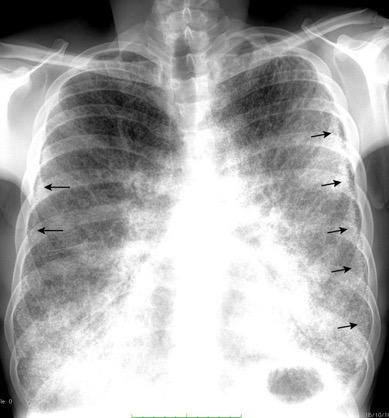

Derrame pleural 43-48% de pacientes con embolismo.

< 1/3 de hemitórax: 90%.(puede haber en lado opuesto).

Siempre exudados.

75% de los pacientes con TEP y derrame pleural tienen dolor pleurítico.

La disnea desproporcionada